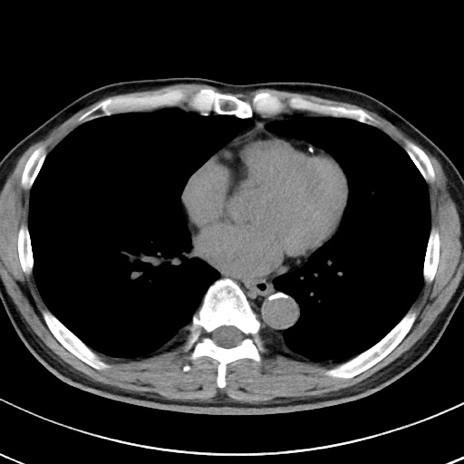

【腹部TIPS】症例29 参考症例 CT(横断像)

症例

70歳代男性